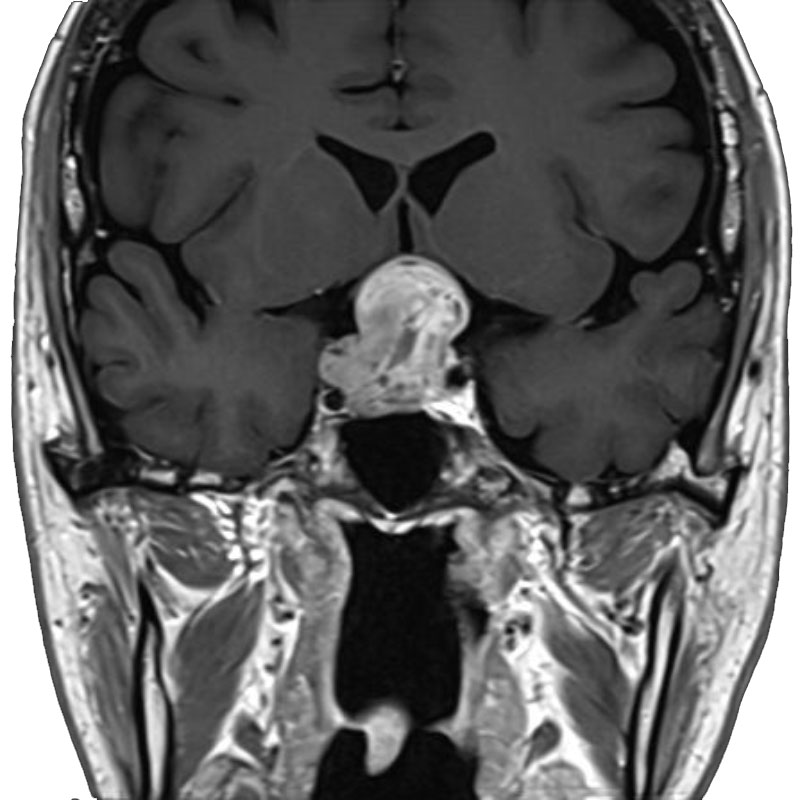

脳動静脈奇形

血管塞栓術

松田/濵田/元永